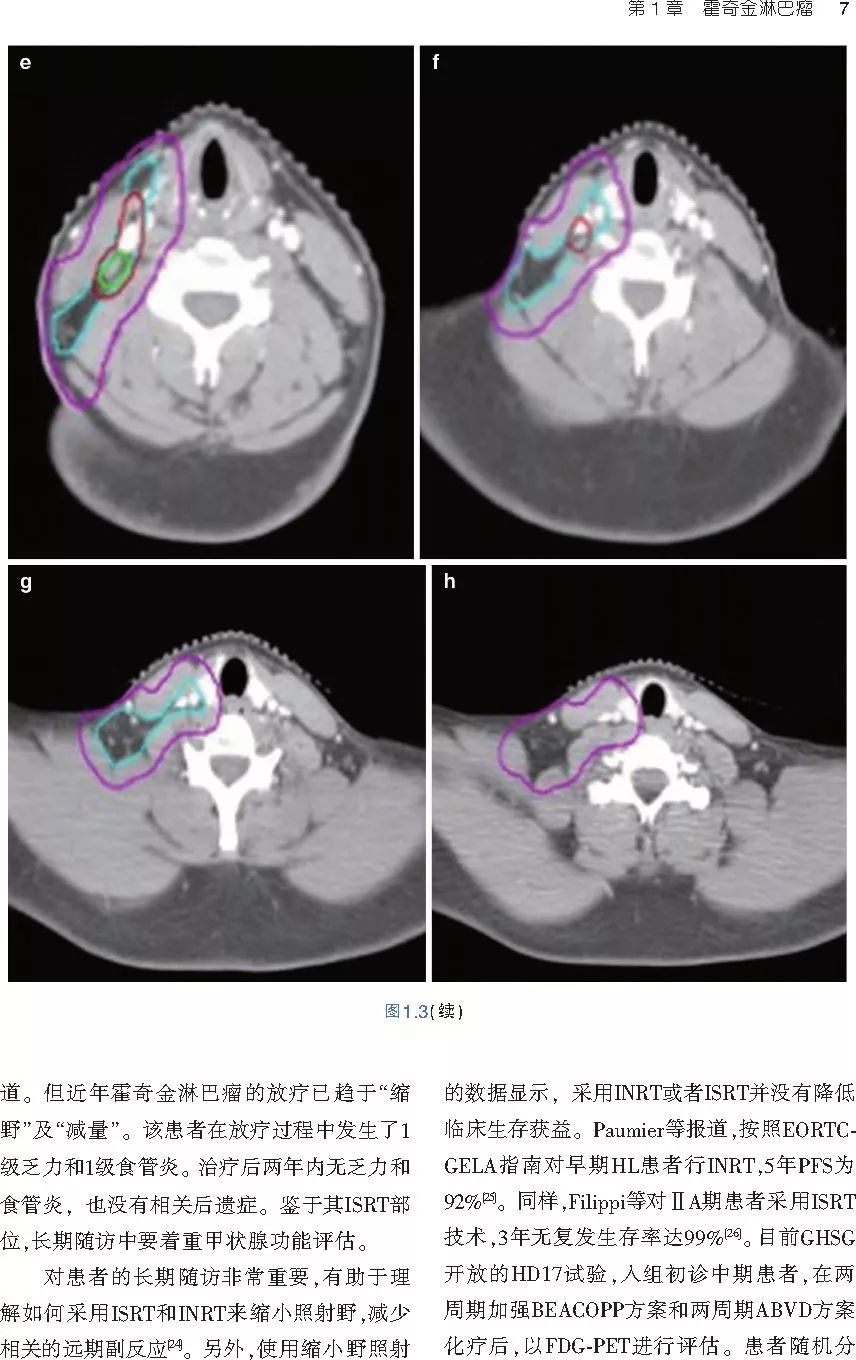

❤ 展开疾病诊断、病理描述及治疗方向的详细阐述,包含医学影像,图文并茂,深入浅出。

本书案例讨论遵循标准格式,包括临床描述,其次是与诊断相关的病理描述和分期,然后详细讨论治疗选择。最后,确定治疗方案,并提供所使用的规划放疗技术/方式的图像。对放射肿瘤医生进行临床决策非常有帮助,对于血液病临床医生也有很好的指导作用。